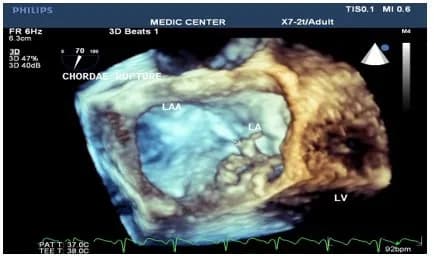

- Đánh giá bệnh lý van hai lá: Trong bệnh lý hở van hai lá, siêu âm tim 3D đóng vai trò quan trọng trong việc đánh giá mức độ hở, cơ chế hở và khả năng sửa van. Siêu âm 3D cũng được sử dụng để hỗ trợ sửa van hai lá qua da bằng thiết bị MitraClip.

- Hình ảnh cấu trúc 3D và chuyển động của tim: Siêu âm tim 3D cung cấp hình ảnh ba chiều về cấu trúc tim và chuyển động của các thành phần tim, đặc biệt là cấu trúc van tim. Điều này giúp bác sĩ hiểu rõ hơn về cơ chế bệnh sinh và lựa chọn phương pháp điều trị phù hợp.